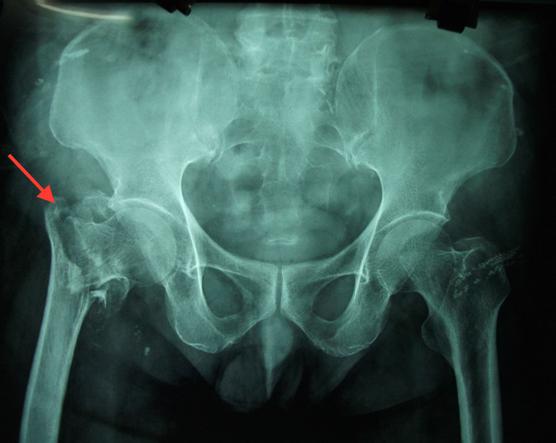

图4 转子下骨折

转子下骨折

在转子下的部位,大部分骨折采用一个长的髓内钉联合粗的拉力螺钉进行固。

图9使用长的髓内钉固定转子下骨折